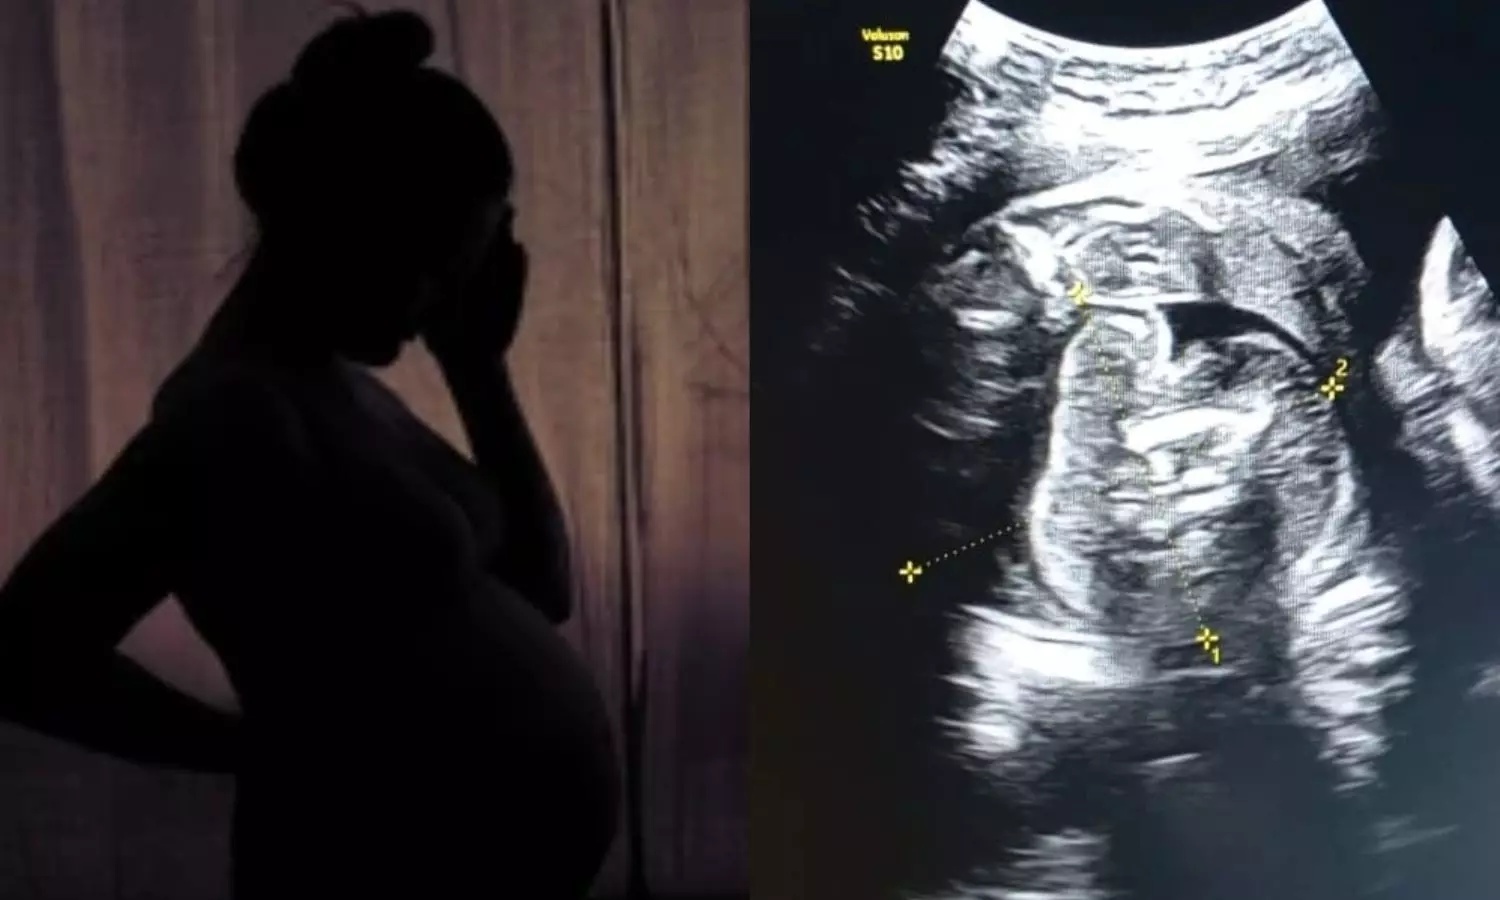

மகாராஷ்டிராவில் கர்ப்பிணி பெண்ணின் கருவிலுள்ள குழந்தைக்குள் கரு வளரும் அரிதினும் அரிதான நிலையை மருத்துவர்கள் கண்டறிந்துள்ளனர்.

மகாராஷ்டிராவில் புல்தானா மாவட்டத்தின் அரசு பெண்கள் மருத்துவமனையில் 35 வார [9 மாத] கர்ப்பிணியான 32 வயது பெண் ஒருவருக்கு சோனோகிராபி செய்தபோது அவரின் ‘கருவில் கரு’ [Foetus inside foetus] வளருவது கண்டறியப்பட்டது.

அதாவது பெண்ணின் வயிற்றுக்குள் உண்டாகியுள்ள குழந்தையின் உடலினுள் மற்றொரு முழு வளர்ச்சியடையாத கரு உருவாகி உள்ளது. இதுகுறித்து அந்த மருத்துவமனையின் மகப்பேறு மருத்துவர் பிரசாத் அகர்வால் கூறுகையில், ஆரம்பத்தில் நான் ஆச்சரியமடைந்தேன், பின்னர் கவனமாக ஸ்கேனை மறுபரிசீலனை செய்தேன்.